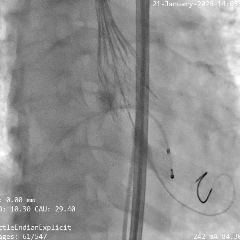

术中影像

根部造影

瓣叶活动差,可见明显反流,猪尾导管测量跨瓣压差约50mmHg

20mm球囊预扩

微腰微漏,左右冠均显影

造影确认瓣环与瓣膜位置

瓣膜0位初始定位释放,展开过程微微下移

全展开位造影评估

瓣膜呈直筒型,微腰,大弯侧约瓣下3mm,少量反流,冠脉显影

瓣膜无张力脱钩

植入后造影评估

瓣膜位置合适,可见少量反流

多角度造影评估

瓣膜形态可,冠脉显影,猪尾测量压差为0